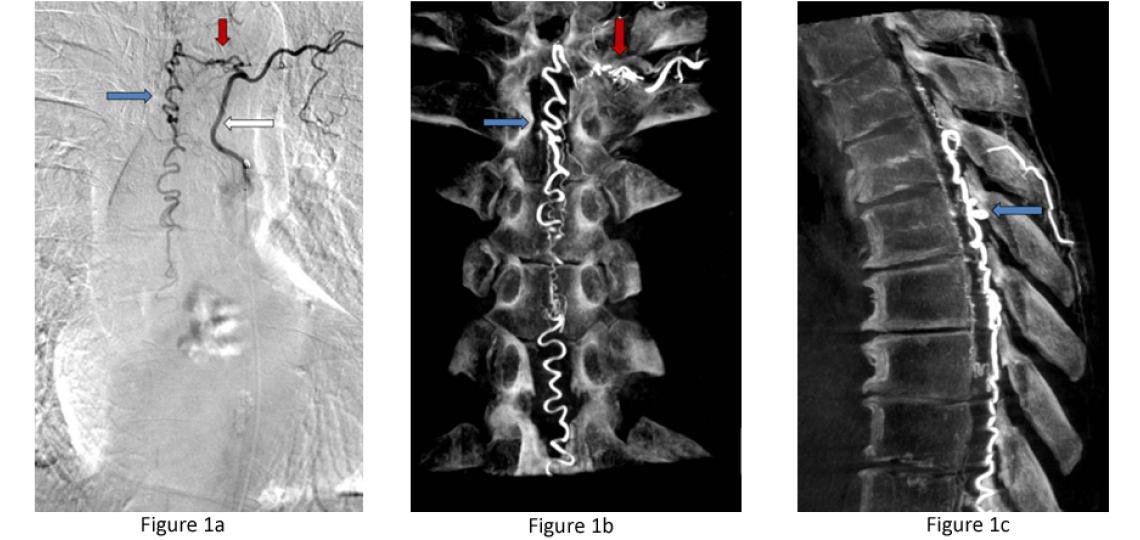

Pial Spinal Arteriovenous Fistulas (Type IV) - Pial AVFs refer to an abnormal connection between an artery and a vein on the surface of the spinal cord. They often come to attention when the vein has enlarged over time due to high pressure from the artery and begins to compress the spinal cord (Figure 2). These are rare lesions.

Figure 2a: Type IV pial spinal arteriovenous fistula – side view or sagittal T2 MRI of the spine showing a massively enlarged spinal vein (red arrow) compressing the spinal cord (white arrow). Figure 2b: A spinal angiogram of the same fistula demonstrating the enlarged artery (white arrow) connecting with the massively enlarged spinal vein (red arrow) and draining vein (blue arrow) leading out of the spinal canal.